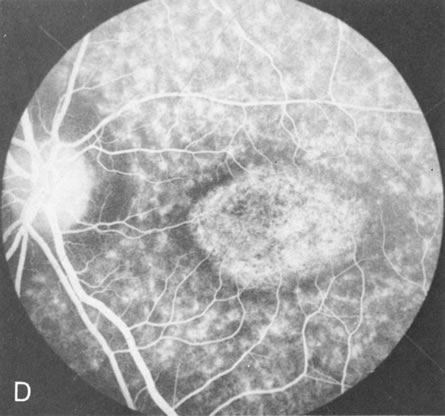

In retinitis pigmentosa (RP), the pigment abnormalities of atrophy, migration, and clumping are made apparent by transmitted hyperfluorescence and blocked hypofluorescence (Fig. 1A). Patients who have very minimal pigmentary alterations (pauci pigmentary RP) or no pigment abnormalities (RP sine pigmento) may show the abnormalities on fluorescien angiography (FA). It is uncommon to see choriocapillaris atrophy except in the late stages. This finding corresponds to the histopathology, which shows that the earliest abnormalities are in the photoreceptors and that the choroid is normal.1

Of more clinical importance is the role of FA in the diagnosis and treatment of cystoid macular edema (CME) (Fig. 1C and D). Stereoscopic FA indicates that the leakage, which may be diffuse or have the typical petaloid stellate appearance of CME, can come from the perifoveal retinal capillaries, from the choroid through the RPE, or from a combination of both sources.4 With the recent suggestion that CME in RP may be successfully treated with acetazolamide,5, 6 FA is thus important to document the diagnosis of CME, establish the origin(s) of leakage, and follow patients during and after therapy.